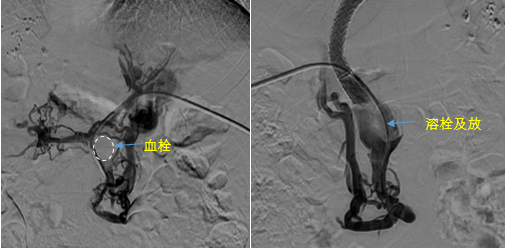

在西安國際醫(yī)學(xué)中心醫(yī)院,韓國宏教授對李女士進(jìn)行了細(xì)致的問診及檢查,在CT圖像上仔細(xì)的分析,針對患者特殊的病情制定了詳細(xì)的治療方案。第一次進(jìn)入手術(shù)室,在DSA的監(jiān)測下,造影過程中門靜脈血栓的輪廓逐漸顯現(xiàn)出來,見多識廣的醫(yī)生們也大吃一驚,發(fā)現(xiàn)遠(yuǎn)端脾靜脈及腸系膜上靜脈也存在大量血栓?;颊叩氖彻芪傅嘴o脈曲張非常嚴(yán)重,疏通堵塞的門靜脈已是刻不容緩。

見此情形,韓國宏教授憑借豐富的臨床經(jīng)驗(yàn)很快調(diào)整了策略,在超聲診療中心的協(xié)助下進(jìn)行門靜脈右支穿刺,并進(jìn)行造影,看到目標(biāo)血管后,韓國宏教授用“明修棧道,暗渡陳倉”的方法,讓來自脾臟和胃腸的血流終于暢通的回流到了肝靜脈。通過血流的沖刷以及抗凝溶栓藥物的作用,幾日后復(fù)查造影發(fā)現(xiàn)門靜脈血栓已逐漸變小,不會對回流到肝臟的血流產(chǎn)生大的阻礙作用,門靜脈的壓力顯著減小,患者再次出血的幾率也隨之降低。幾經(jīng)周折,這顆“定時(shí)炸彈”終于被拆除,李女士和她的家人多年來心里的石頭也終于落地。